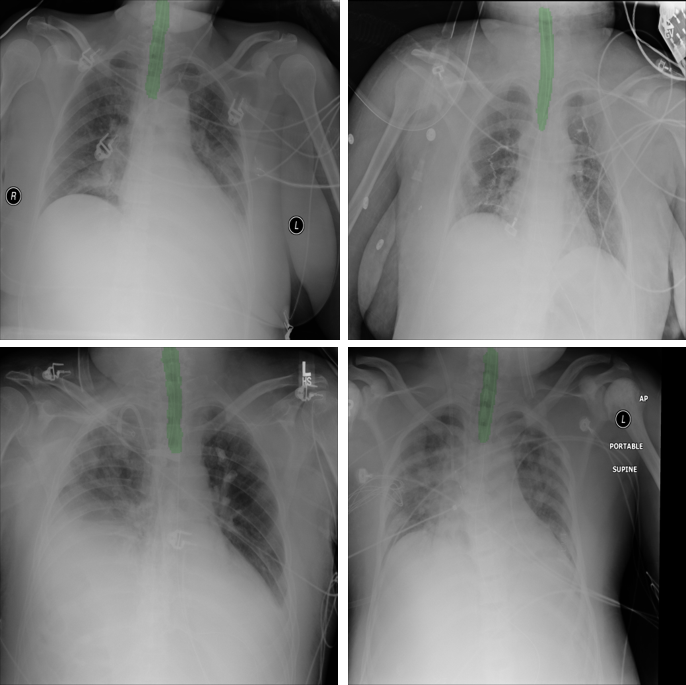

Figure 6: Cases correctly classified with ET tube and their corresponding segmentation as overlay (in green color)

Refer to caption

Training the combined model for classification and segmentation of ET tubes on synthetic X-ray images, we reached an AUC of 0.962 in classification accuracy. Using fine-tuning on real X-ray images, the accuracy improved to an AUC of 0.987 with both sensitivity and specificity over 95% (Figure 6). Figure 6 shows real chest radiographs from the test set that were classified correctly for presence of ET tube and their output segmentation maps.